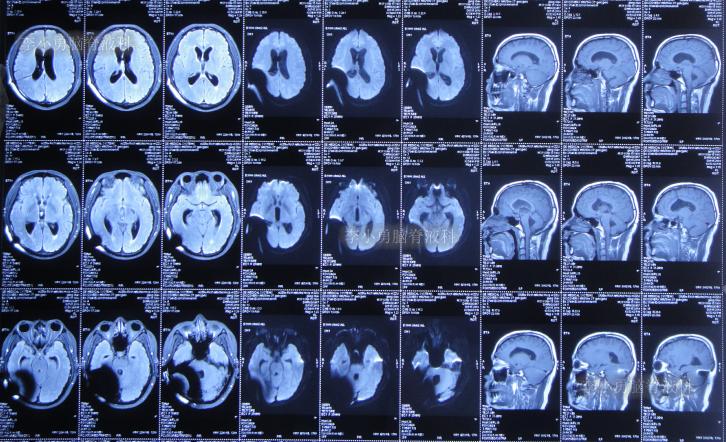

于是次日即2019年10月4日,第3次就诊于给予手术的省级三甲医院,入院次日查头颅核磁(图-2)后考虑引流管堵塞,给予了脑室分流管探查调整术。

图-2:2019年10月5日头颅核磁

脑室分流管探查调整术后5天即2019年10月10日,患者症状好转,查头颅CT示脑室缩小(图-3)。

图-3:2019年10月10日头颅CT